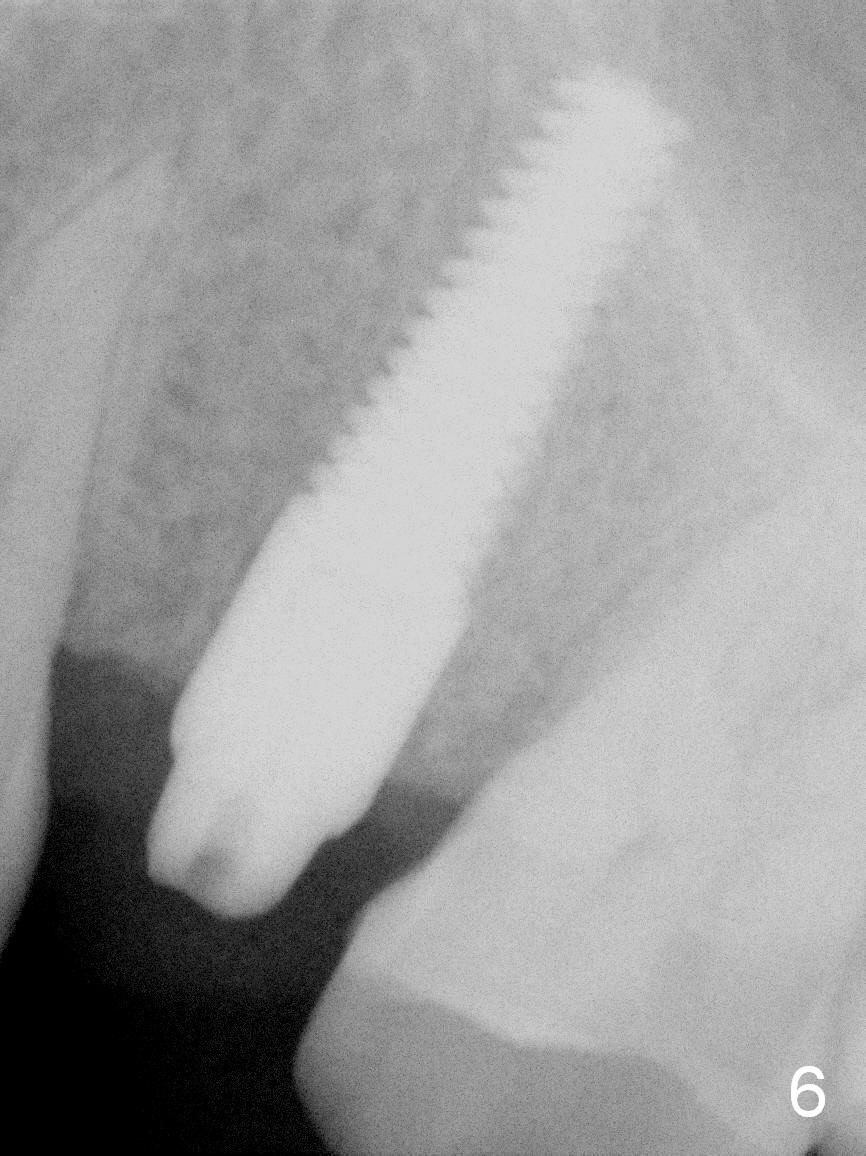

The immediate provisional is found to be fractured 4 months postop. PA is taken to confirm osteointegration (Fig.6 periimplant space closed). With implant threads buried deep in the bone, there is less likelihood to develop periimplantitis.